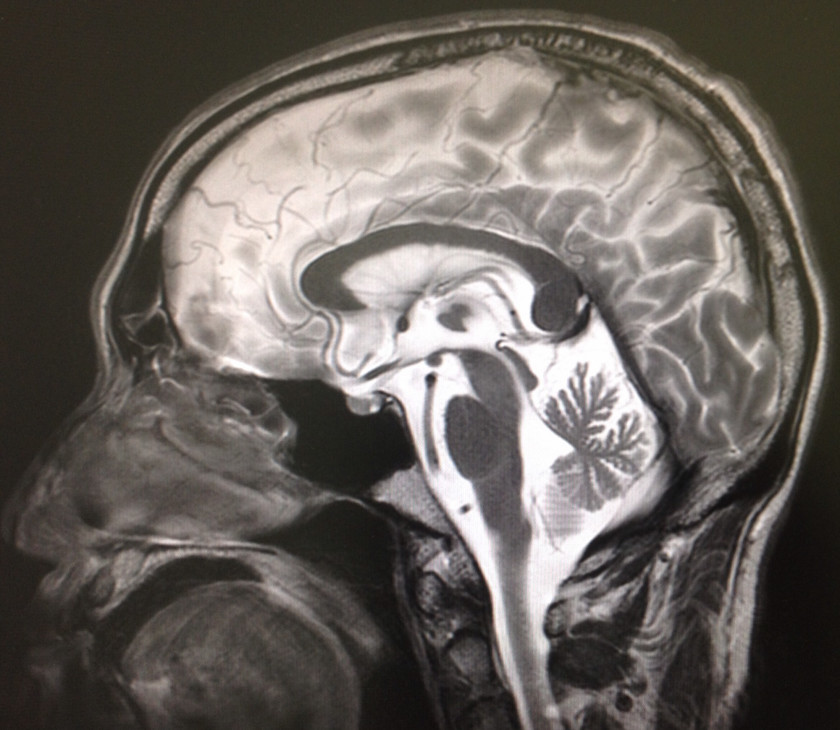

2018/06/05 急に歩けなくなったアルツハイマー症例

改訂長谷川式 11/30 遅延再生 0/6 頭部MRI(受診時)前頭葉と両側海馬の萎縮 錐体外路兆候及び行動異常 認めず。今年、3月初めに転倒。頭部CT上、血腫認めず。4月中旬、代診だったが、トイレに歩いて行けている、夜間に家の中を歩き回って困る等、歩行障害はなかった。5月中旬、「歩けなくなった」と受診。見当はついているので、脳外科を紹介。その返事に同封されていた写真が上のもの。無事にオペも終わり、元気であると、わざわざ、御家族が御礼の挨拶に来院され、近況を聞くことができた。でも、両側に血腫があるとは思っていませんでした。

80歳代 女性。昨年末から診療開始。改訂長谷川式 11/30 遅延再生 0/6 頭部MRI(受診時)前頭葉と両側海馬の萎縮 錐体外路兆候及び行動異常 認めず。今年、3月初めに転倒。頭部CT上、血腫認めず。4月中旬、代診だったが、トイレに歩いて行けている、夜間に家の中を歩き回って困る等、歩行障害はなかった。5月中旬、「歩けなくなった」と受診。見当はついているので、脳外科を紹介。その返事に同封されていた写真が上のもの。無事にオペも終わり、元気であると、わざわざ、御家族が御礼の挨拶に来院され、近況を聞くことができた。でも、両側に血腫があるとは思っていませんでした。